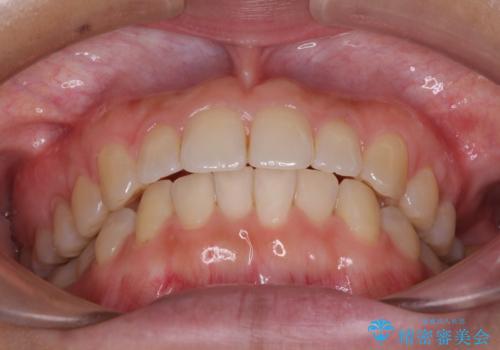

インプラントによる補綴治療とインビザライン矯正

- 抜歯が必要と診断された奥歯を気にして来院された患者様です。

抜歯の上インプラントによる補綴治療を行うこととなりましたが、前歯の叢生も気になるとのことで並行して矯正治療を行うこととしました。

歯列不正は軽微であったので、インビザラインによる矯正治療とし、矯正治療中にインプラント埋入を行う予定としました。

痛みがないので、ボロボロのまま放置していましたが、抜歯後は汚れが溜まりにくくなりスッキリとしたようです。

前歯のデコボコも解消され、ブラッシングが楽になりました。